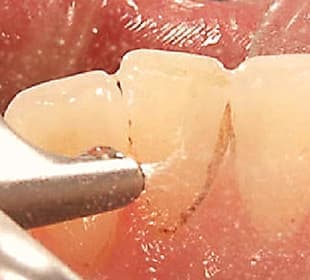

マイクロスコープ(歯科手術用顕微鏡)

お口の中の細かい部位をしっかり把握して一連の処置ができるように、患部を拡大視しながら治療する機器です。裸眼の数倍から数十倍の大きさに見えるので、より精密な治療が可能。「三好歯科 自由が丘」では歯科医師の間でも信頼性の高いカールツァイス製機器を活用しています。 マイクロスコープが現れ、日本の歯科医療は変わりました。従来の治療ではまず見ることが不可能だった部位を、直接目で見ながら治療を行えるようになり、精密な治療によって予後に明らかな差が出るようになりました。

マイクロスコープを導入している日本の歯科医院はまだ全体の1割未満です。しかしながら、導入していればそれで良いかというと、そうではありません。マイクロスコープを購入すること自体は難しくありませんが、この優れた機器に精通し、使いこなすには、何年も研鑽を重ねる必要があります。 当院ではマイクロスコープによる精密な根管治療を専門に行っているドクターが在籍しております。